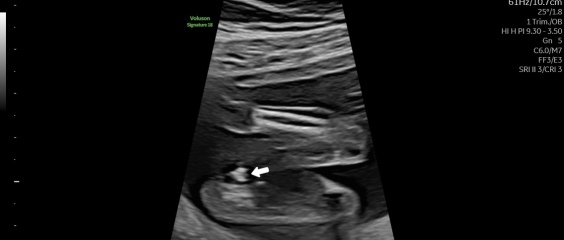

Unsure about gender scan result after conflicting opinions on the images

So we had our gender scan today at 16+3 and the potty shot isn’t as clear as my first child so curiosity had me put it into chat gpt and both pictures said the opposite gender🥲 so can I get some opinions please😂